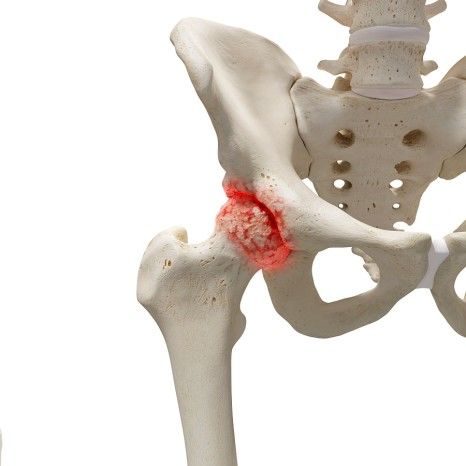

대퇴골두

대퇴골의 윗부분으로 구형의 구조이며, 비구에 꼭 맞게 들어가 고관절의 회전 운동을 가능하게 합니다. 혈액 공급이 취약한 부위이기 때문에 무혈성 괴사가 발생할 수 있습니다.

대퇴골두와 대퇴골 몸통을 연결하는 부위로 체중이 집중되면서 골절이 자주 발생하는 곳입니다. 특히 고령자에서는 골다공증으로 인해 이 부위 골절이 흔하고, 수술이 필요한 경우가 많습니다.

고관절 골절은 주로 대퇴경부나 대전자 부위에 발생하며, 뼈의 구조적 손상에 따라 다양한 증상이 나타납니다.

골절 고정 수술

고관절 골절이 이동되거나 불안정한 경우에는 골절 고정 수술을 시행합니다. 대퇴경부나 대전자 골절이 발생한 경우, 나사못, 플레이트 등의 금속 장치를 사용하여 골절 부위를 고정합니다.